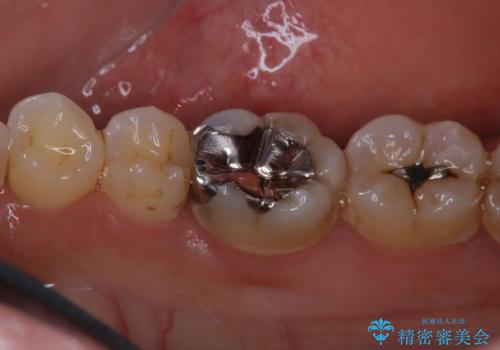

- 銀歯のやり替えをご希望された患者様です。手前の歯にもプラスチックと歯の間に虫歯が出来ていたため、両方とも適合の良いセラミックで補綴しました。

- セラミックインレー7.7万円・仮歯1.1万円・フルジルコニアクラウン7.7万円(税込)費用は治療当時の料金となります